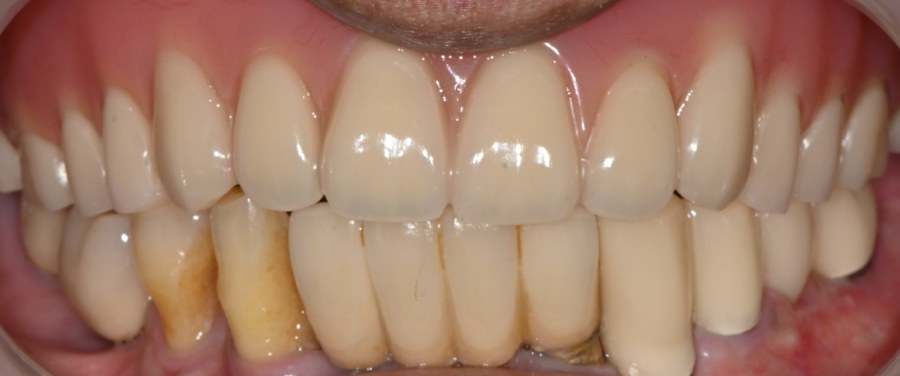

④ Final denture placement

After rechecking the color, height, and bite,

the full maxillary denture was safely placed.

Right after placement,

the patient said,

"The chewing feeling is much more stable."

which made us feel very rewarded.

The discomfort was greatly reduced

When the patient returned two weeks later,

• the denture adapted more stably to the gums

• the feeling of pain only on the left side disappeared

• eating became less uncomfortable

• confidence when speaking while going out improved

As the full denture fit the gums precisely,

the stress felt in everyday life

was greatly reduced.